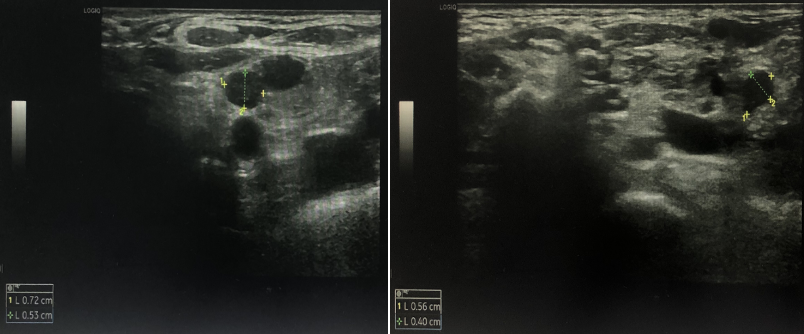

双锁骨上淋巴结超声:双侧锁骨上低回声结节,考虑异常肿大淋巴结。

胸部CT:纵隔及右肺门多发淋巴结,部分肿大,较前新增,双侧胸腔积液

伴双肺局部膨胀不全,较前进展。